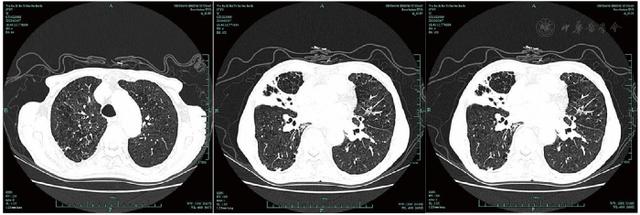

共317例TOPD患者完成影像學檢查。TOPD患者肺部CT顯示多處鈣化結(jié)節(jié)等結(jié)核瘢痕,部分患者存在一定程度的肺氣腫和支氣管擴張征象,見圖1,圖2,圖3。TOPD患者左肺上、舌、下葉的結(jié)核瘢痕陽性分別為176例(55.5%)、120例(37.9%)和126例(39.7%),右肺上、中、下葉的結(jié)核瘢痕陽性分別為215例(67.8%)、142例(44.8%)、168例(52.9%);左肺的支氣管擴張征象主要集中在左肺舌葉,右肺主要位于中葉、下葉;肺氣腫在雙肺間分布較為均衡,見圖4。

Figure 3

Figure 3 Pulmonary imaging findings of TOPD patients